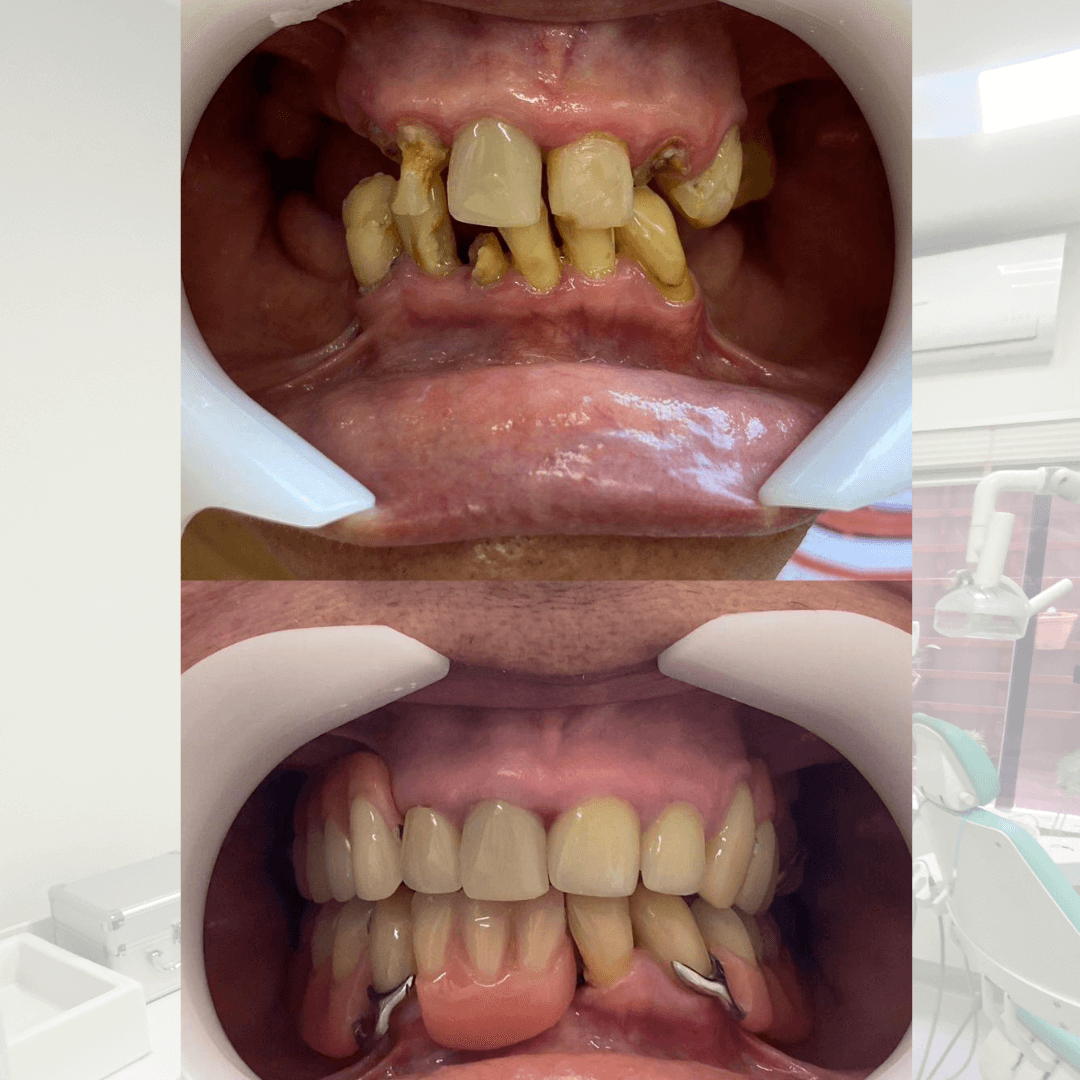

Tenho forte afinidade pela Endodontia, além de ampla experiência em reconstrução de dentes severamente destruídos e restaurações estéticas.